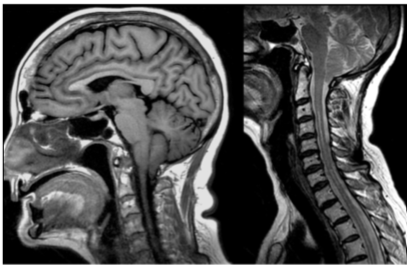

Paciente do sexo feminino, de 63 anos, realiza estudo por ressonância magnética para avaliação de cefaleia, sendo diagnosticado malformação de Chiari tipo I.

A respeito das características da malformação de Chiari tipo I tem-se que:

Paciente do sexo feminino, de 25 anos, sob suspeita clínica de doença desmielinizante, realiza ressonância magnética do crânio e das colunas cervical e dorsal. No relatório, são descritas lesões ovaladas com hipersinal em T2/FLAIR nas seguintes localizações: justa-corticais, periventriculares, ponte e coluna cervical, sendo que algumas delas apresentam realce pelo meio de contraste.

Considerando-se os conceitos definidos pelos critérios revisados de MacDonald (2017), conclui-se que: